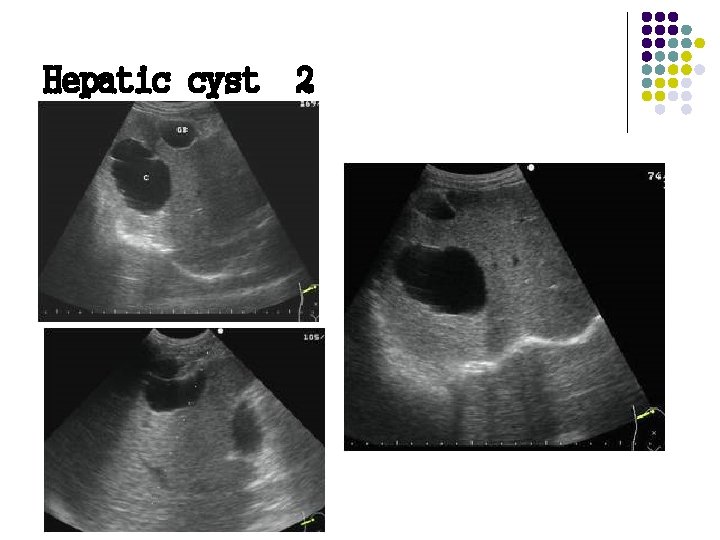

Ultrasound Findings of Cystic Lesions On ultrasound examination the cyst walls are thin , with well-defined borders, and anechoic with distal posterior enhancement.

Sonographic Features Of hepatic cyst: l No internal echoes l Smooth borders l Regular /irregular outline l Acoustic enhancement l Septum may be seen

Hepatic cyst 2

Hepatic cyst Second most common benign hepatic lesion(22%) l Acquired hepatic cyst: second to trauma, inflammation , parasitic infection l Associated tuberous necrosis polycystic kidney disease(25 -33%have liver cyst); polycystic liver disease(50%have polycystic kidney disease) l